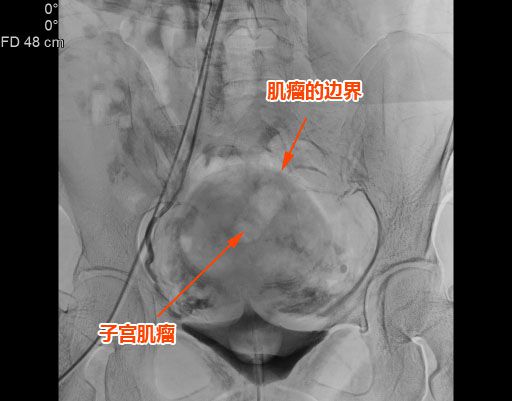

△子宮肌瘤巨大,邊界清晰。

該名患者來自揭西,有下腹痛1個多月,腹部外觀像孕婦,經影像學檢查可見子宮前壁肌間有1個7.5cm左右的巨大肌瘤。此類患者如采用腹腔鏡或傳統手術治療,需要做子宮切除手術。患者因年紀僅40餘歲,相對較輕,想要保住子宮。

随後,李旭丹主任與胡志華主任聯手爲患者實施手術,通過患者股動脈穿刺,置入微導絲、導管,經動脈自然腔道将導管送達左右側髂總動脈進行造影,可見肌瘤供血血管,随後利用微導管将特制栓塞材料送達子宮動脈進行栓塞。造影顯示子宮肌瘤供血已被掐斷,順利完成手術。